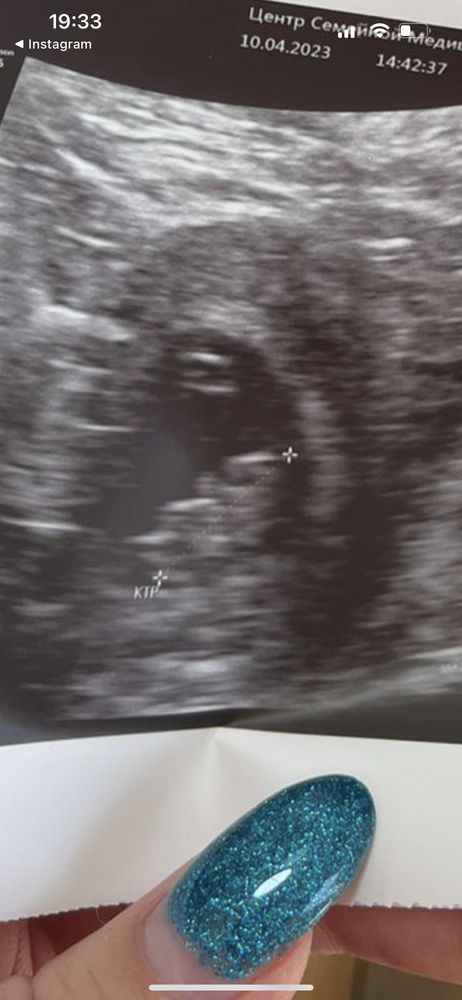

Приём, 8я неделя 🥰

Врач тут все рассмотрела, говорит слева голова, ручки ножки видно, а я вижу только комочек 😅

Вижу лапку)) к эндокринологу сходите обязательно, ттг и глюкоза связаны, у меня тоже с беременностью сильно повышается ттг, назначит вам препараты и всё хорошо будет)

Алисия, направили в клинику алмазова, там говорят сильные специалисты сидят 🙏 где увидели?)) мне покажите, пожалуйста))